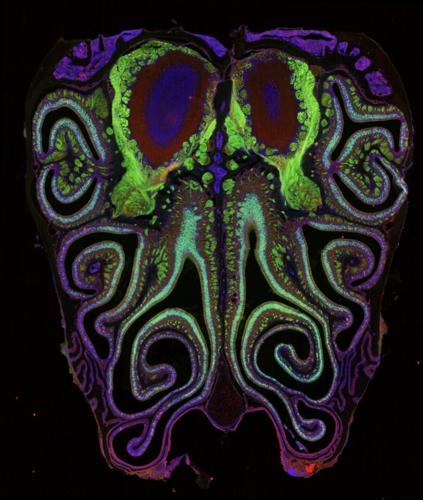

A microscope photo of a cross section of a mouse nose. The mouse was genetically modified to express green fluorescent protein in smell neurons. A small subset of dying neurons is labeled in red. (Datta Lab via SWNS)

A map of the thousand types of smell receptors in the olfactory tissue of a mouse nose, labeled by a color gradient. The bottom inset shows the precise spatial positions of a tagged subset of receptors. (Datta Lab via SWNS)